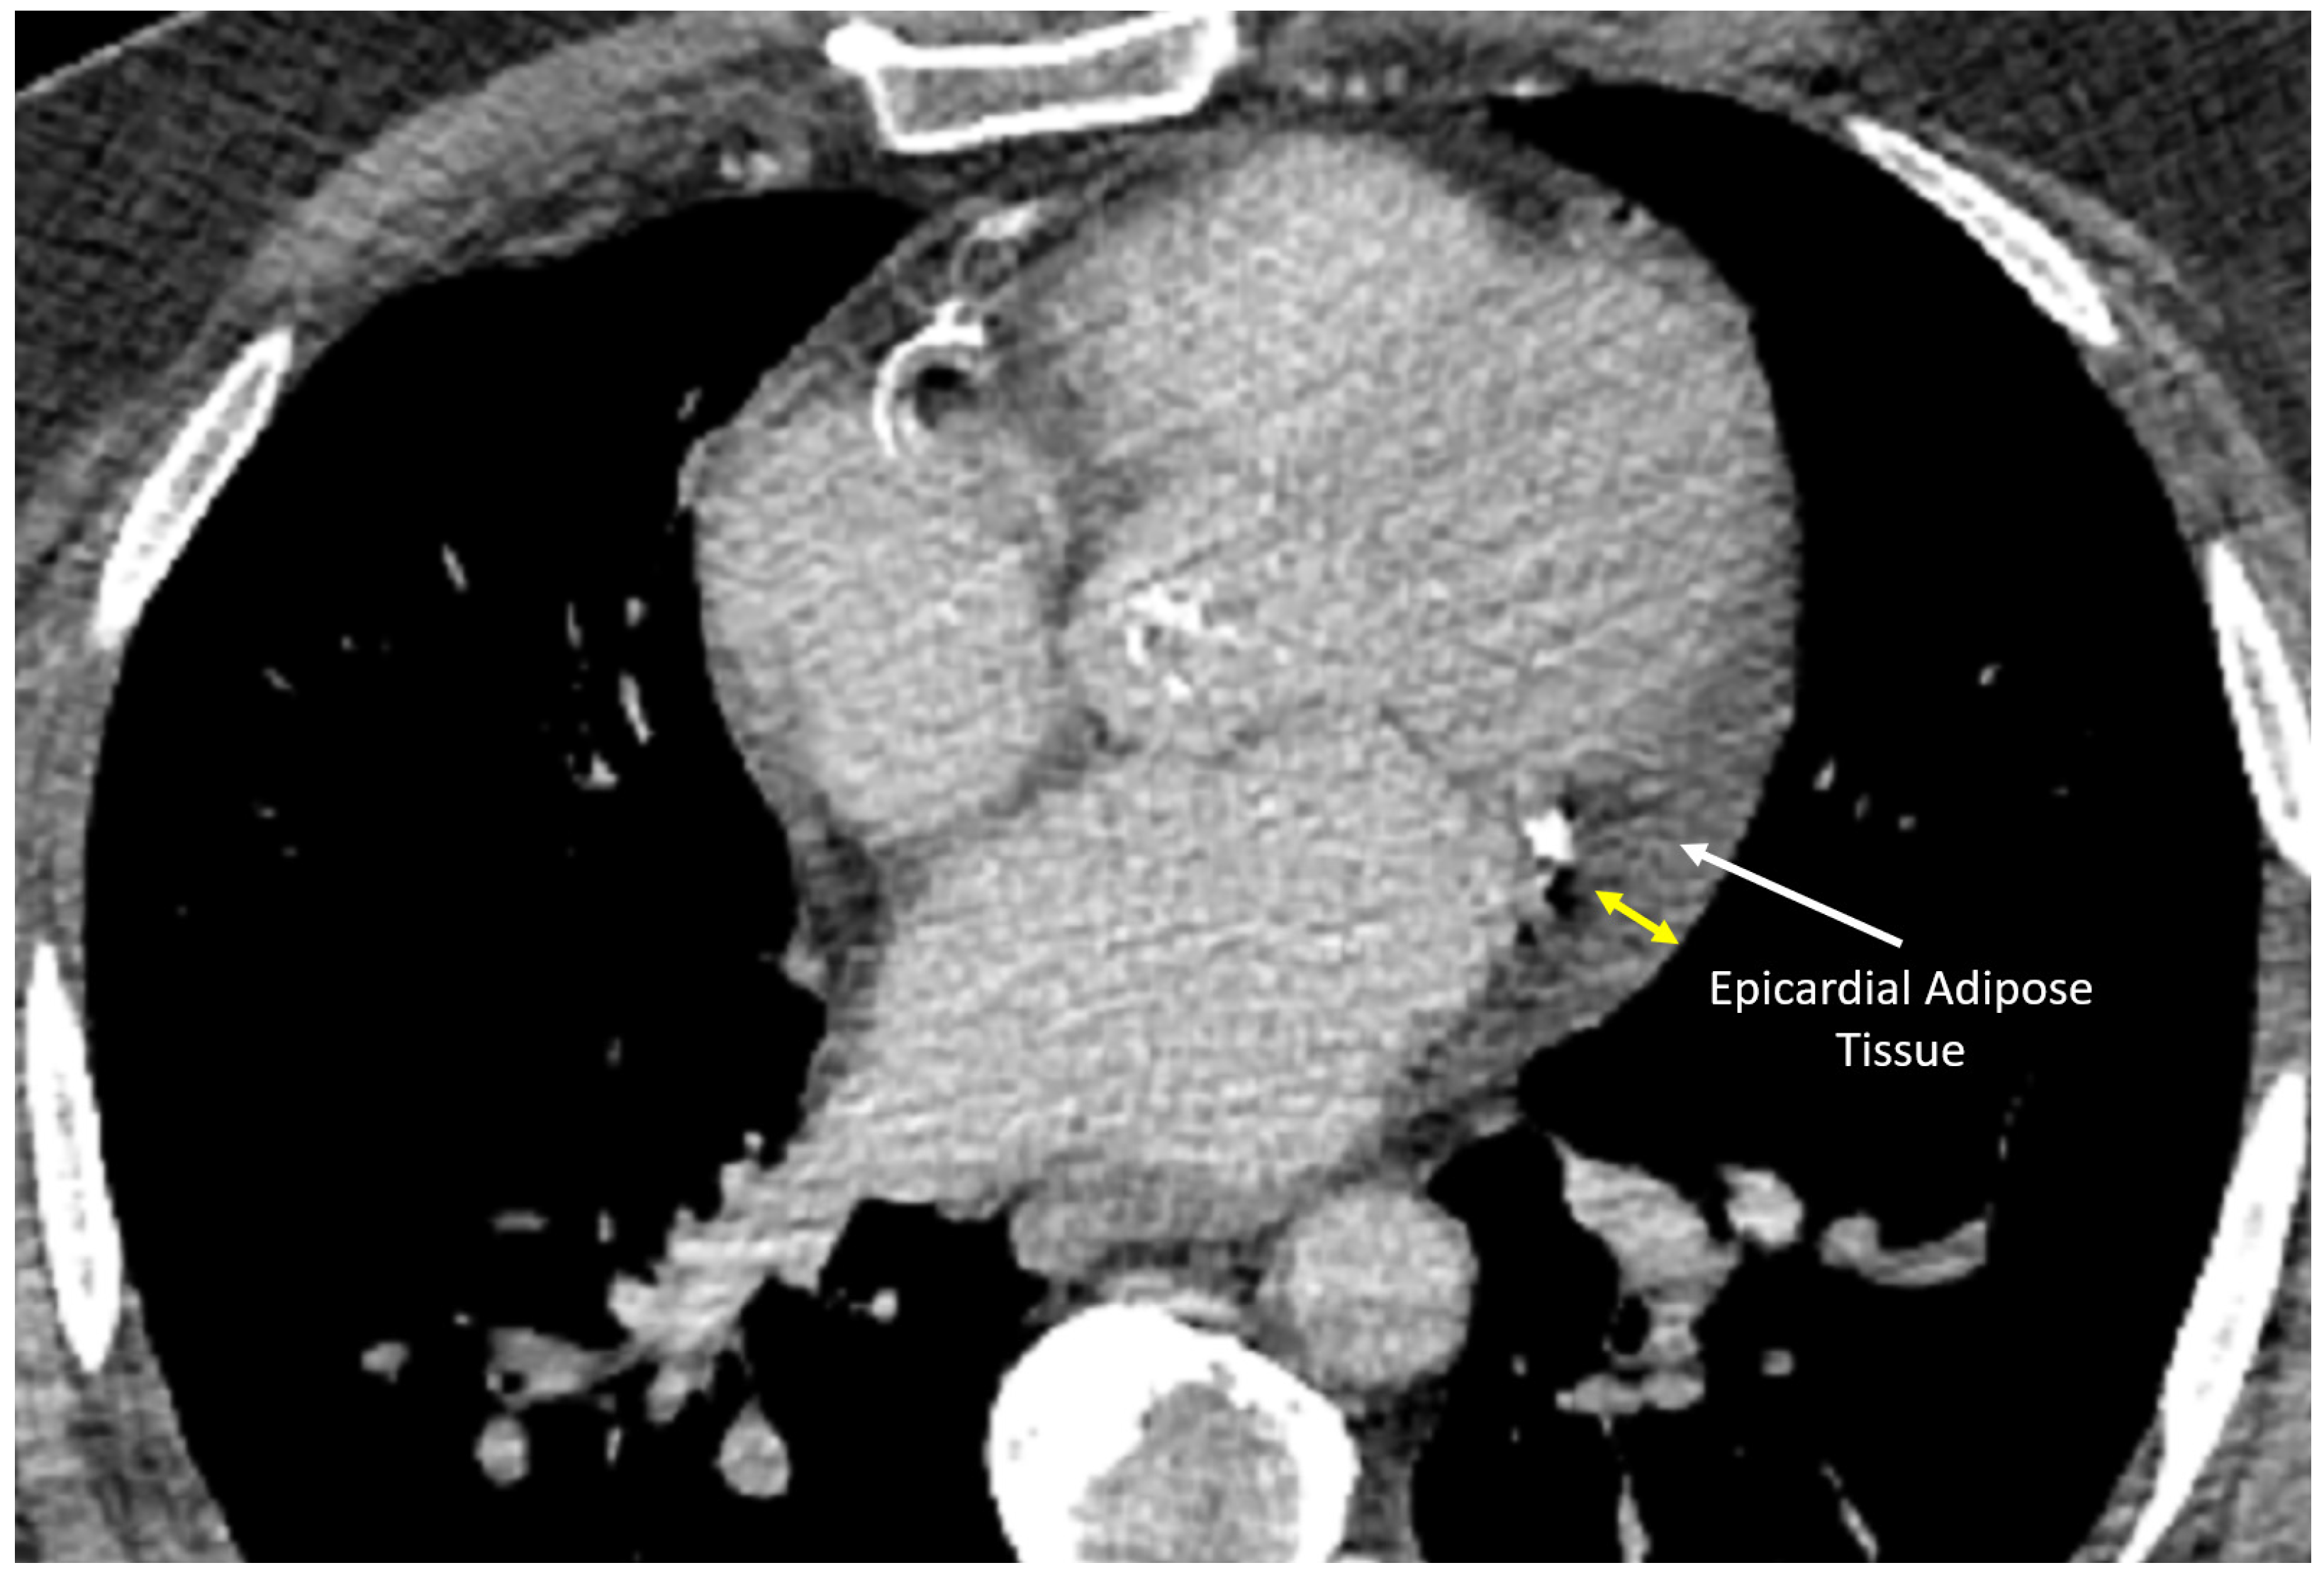

11. Advanced Imaging

Cardiac computed tomography (Figure 8), cardiac magnetic resonance (CMR), and nuclear medicine techniques offer advanced imaging capabilities for assessing atrial pathophysiology and EAT. CMR, with its high spatial resolution and late gadolinium enhancement (LGE), allows precise quantification of atrial fibrosis and EAT volume, complementing echocardiographic strain analysis by providing direct visualization of structural remodeling [77]. Nuclear imaging, such as PET with 18F-FDG tracers, evaluates metabolic activity and inflammation in EAT but is less accessible and more invasive [78].

Figure 8.

Computed tomography scan of the chest showing the cardiovascular structures and epicardial adipose tissue (arrow).

In healthy hearts, epicardial fat is minimal, with normal epicardial fat thickness generally under 5 mm and atrial adiposity largely absent or undetectable within the myocardium. In AF patients, epicardial fat thickness often increases to 6–8 mm or more, and atrial adipose infiltration is significantly higher, typically 20–30% above normal levels.

In cases of AF combined with fibrosis, atrial adiposity can rise by up to 30–50% compared to normal hearts, with fibrotic tissue comprising 10–25% of the atrial wall, as identified via LGE in CMR. Adipose tissue frequently co-localizes with fibrosis, creating a structural and electrical substrate for AF progression. CMR techniques such as fat–water separation and T1 mapping are essential for quantifying these abnormalities, offering precise insights into the relationship between adiposity, fibrosis, and disease severity.